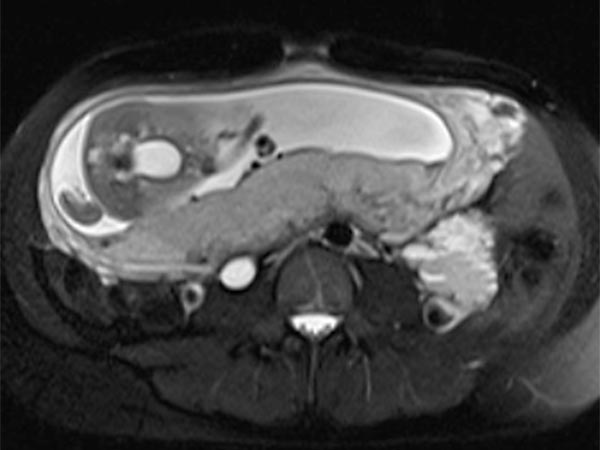

Koronare und axiale T2-gewichtete Haste-Sequenzen ohne Kontrastmittel 8 Wochen nach der Entbindung. Postpartal zeigt sich wieder eine deutliche Größenreduktion der venösen Malformation.

Die venöse Malformation zeigt 8 Wochen nach Entbindung bereits wieder eine deutliche Größenregredienz, sodass bei der stillenden Mutter aktuell keine minimalinvasive Behandlung mittels Sklerotherapie notwendig ist. Die große venöse Malformation war zu diesem Zeitpunkt auch asymptomatisch.